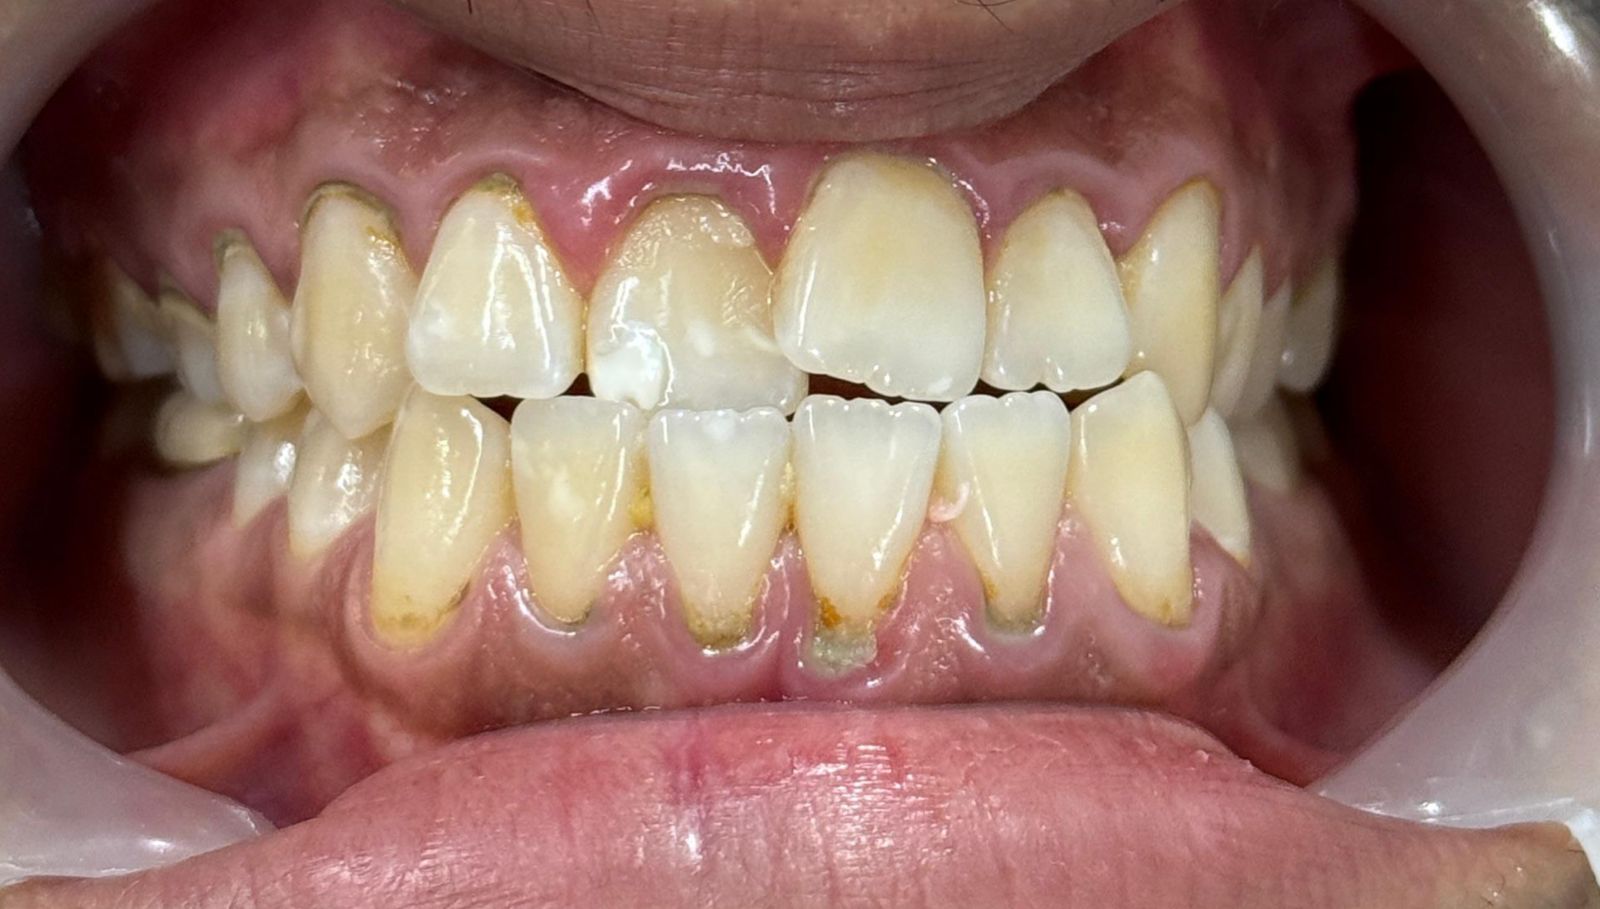

Before & After Results

At Aline Dent, we take pride in delivering visible and lasting improvements in our patients’ smiles. Our before-and-after results highlight the effectiveness of modern dental treatments combined with personalized care. This gallery showcases real dental cases treated at our clinic, giving you a clear idea of how different dental concerns can be corrected with the right treatment approach.

From minor corrections to complete smile enhancements, these teeth transformation results demonstrate how professional dental care can improve both oral health and appearance. Our experienced dental team carefully evaluates each patient’s needs and creates customized treatment plans to achieve natural, healthy, and confident smiles.

In this gallery, you will find a variety of smile makeover cases, including treatments for crooked teeth, gaps, discoloration, damaged teeth, and other common dental concerns.